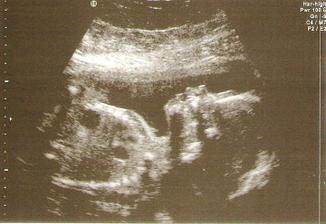

17.5 velký UTZ a véééliké očekávání...moc krásné to bylo, manža byl ve vytržení máme potvrzené že to je holčička a pan dr. se vyjádřil, že hledala dlouho nějakou vadu ale nic nenašel 😀 tak jsme šťastní jak blechy.